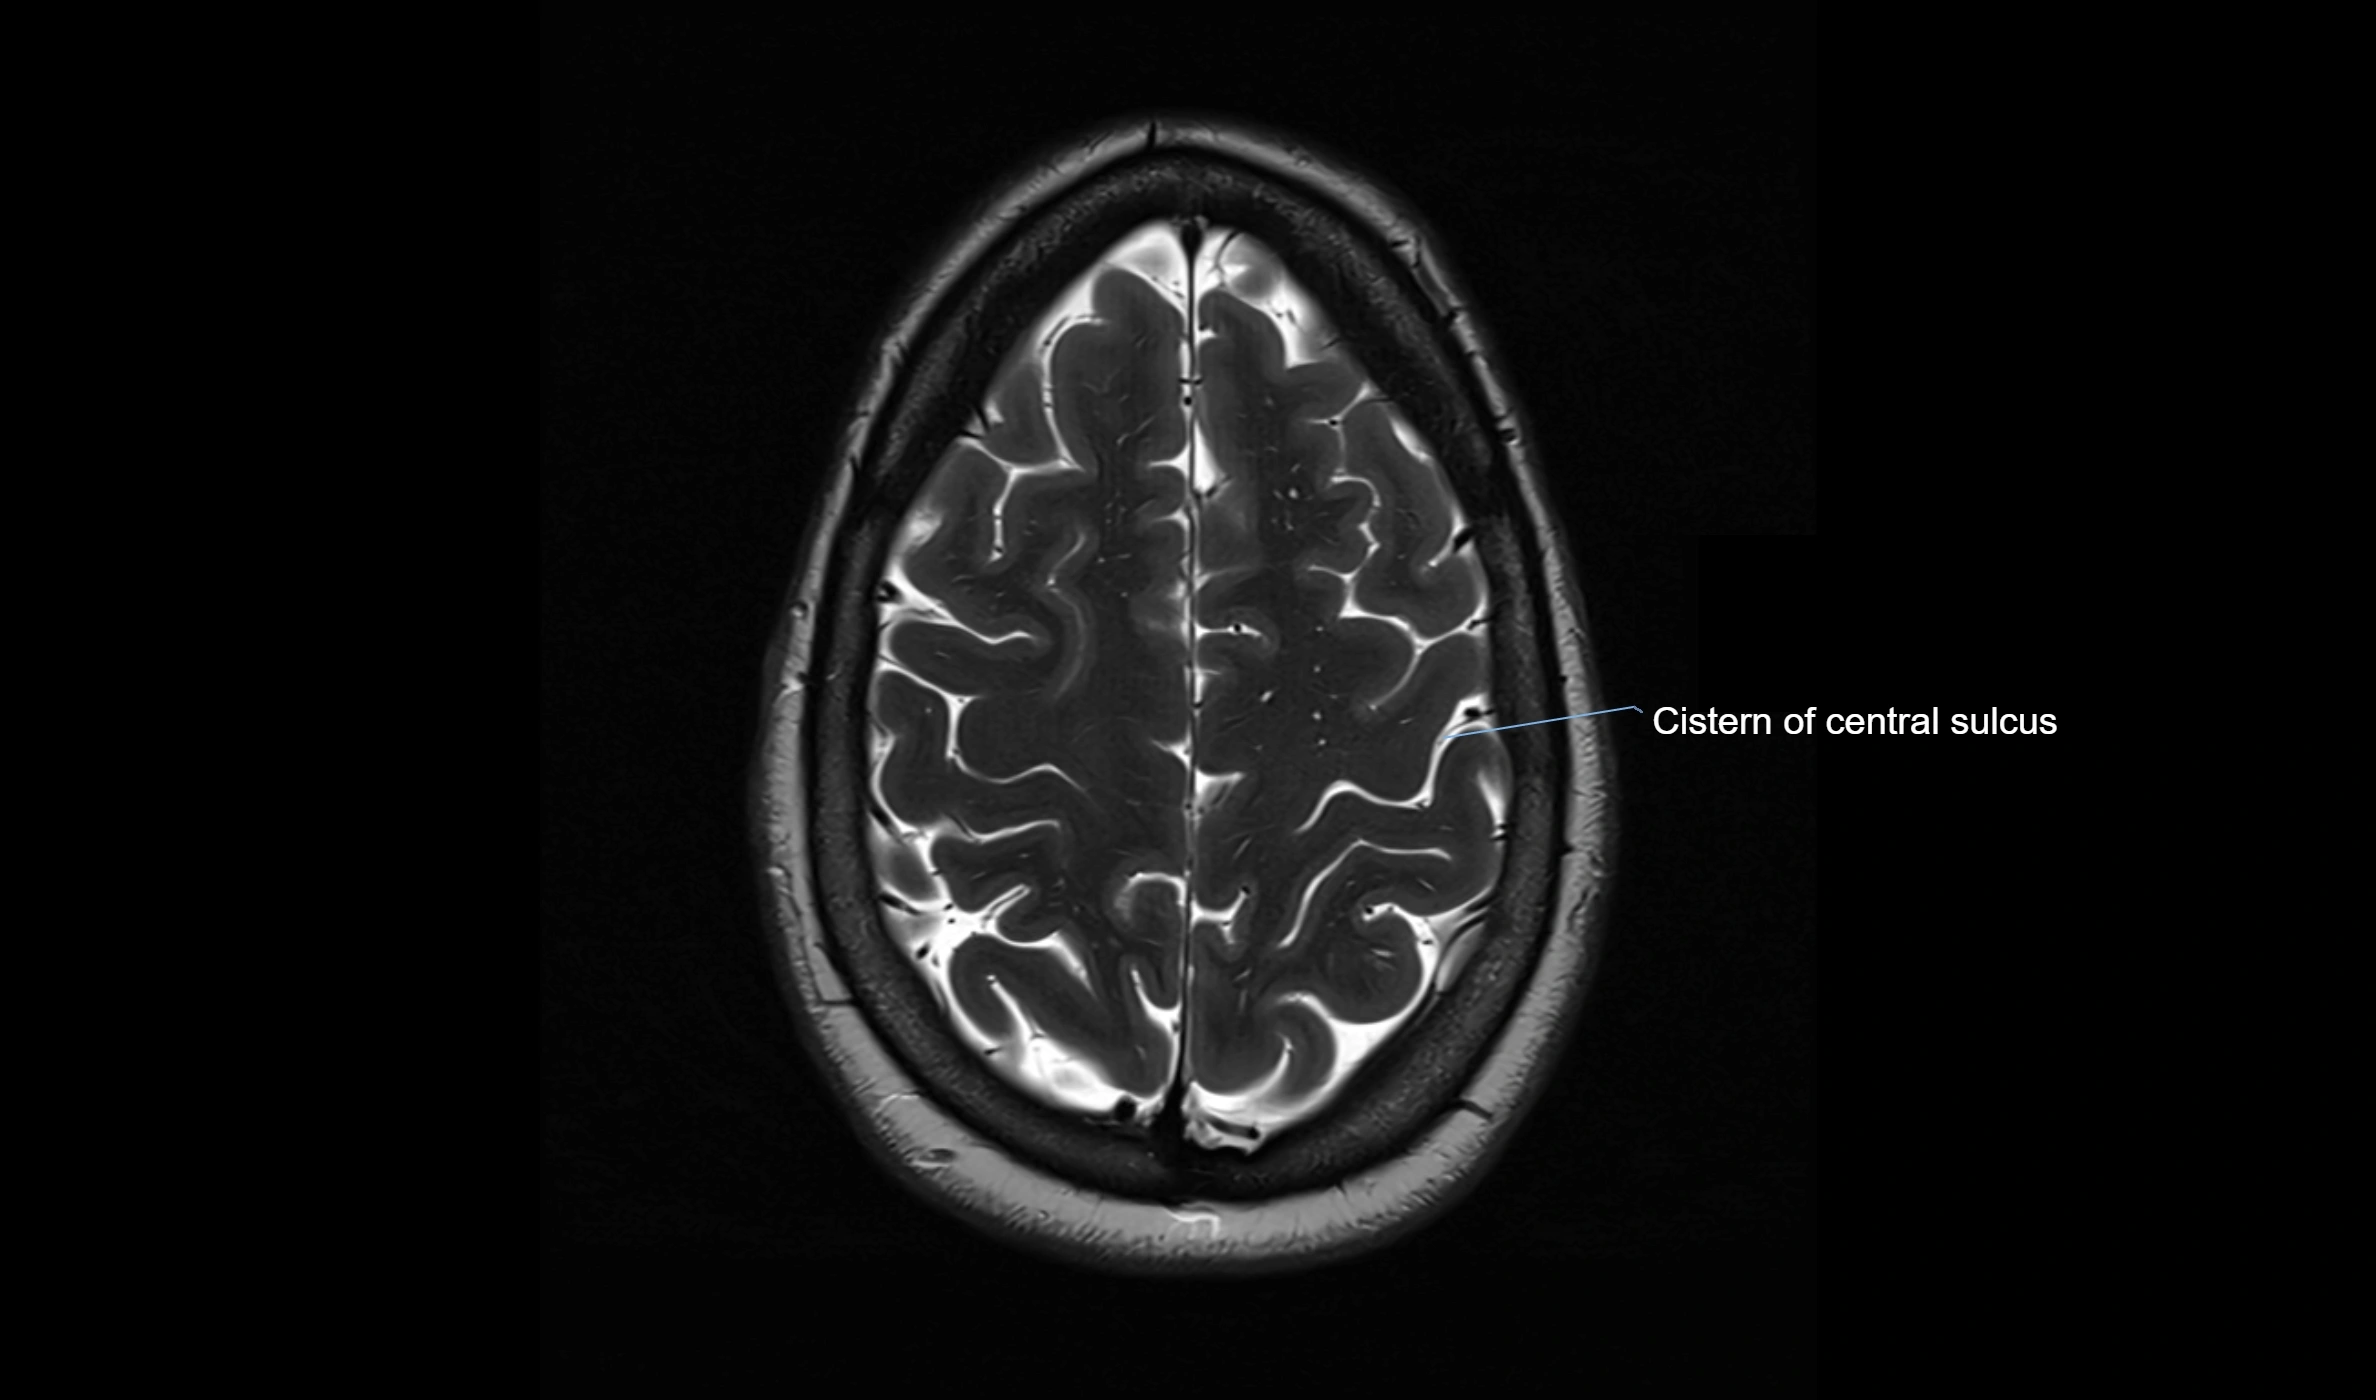

The ambient cistern is a paired, narrow, and elongated subarachnoid space located bilaterally along the lateral aspect of the midbrain. It serves as a conduit between the interpeduncular cistern anteriorly and the quadrigeminal cistern posteriorly. This cistern houses critical neurovascular structures, including parts of the posterior cerebral artery, superior cerebellar artery, trochlear nerve (cranial nerve IV), and the basal vein of Rosenthal. It plays an important role in the circulation of cerebrospinal fluid (CSF) and provides an anatomical corridor for various vessels and nerves passing around the midbrain.

MRI Appearance

• T2-weighted images:

• The cistern is hyperintense (bright) due to the high water content of CSF.